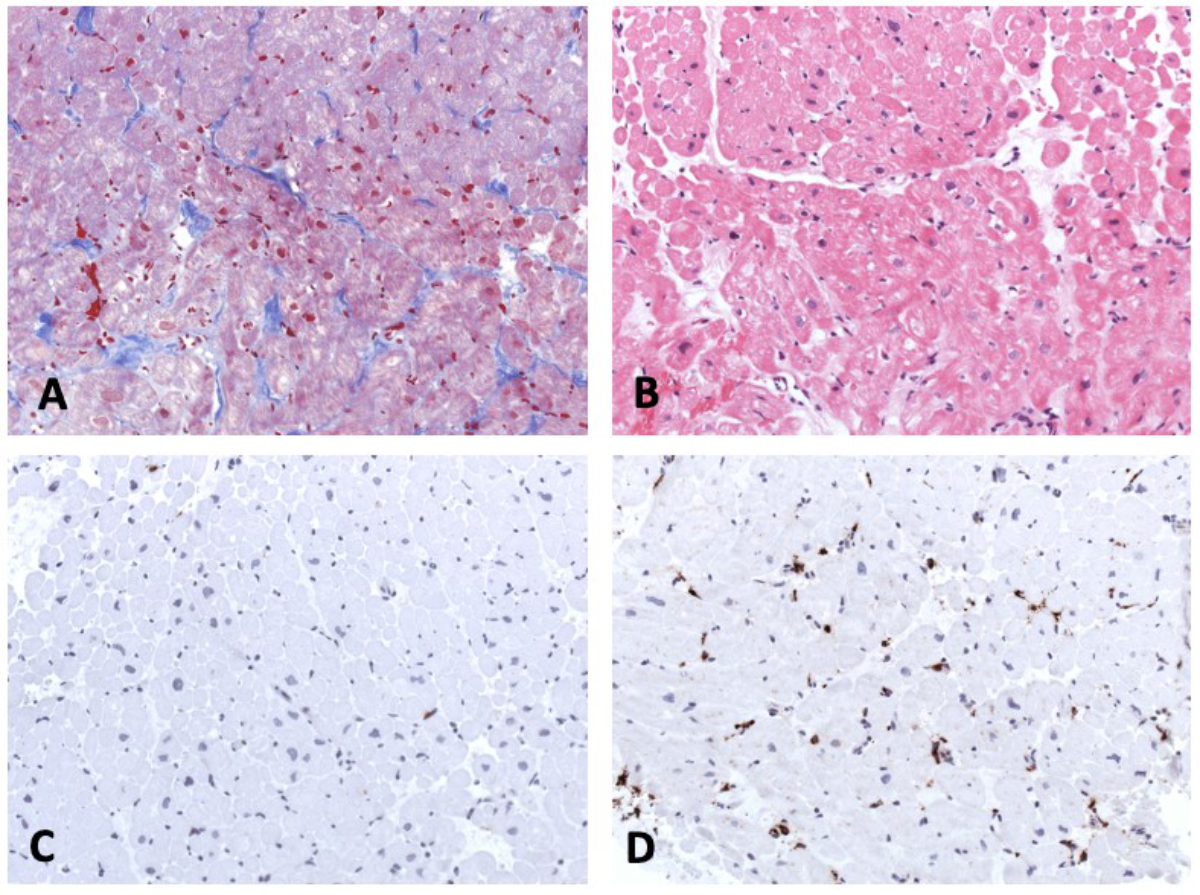

Six days after admission, the cardiac haemodynamics was invasively evaluated with a cardiac catheterisation and showed a normal left ventricular end-diastolic pressure without pulmonary hypertension. Coronary anomaly was ruled out. A total of 12 endomyocardial biopsies were taken from the lateral wall and septum of the right ventricle. The histological results (fig. 4) were not consistent with an acute/chronic lymphocytic, eosinophilic, or giant-cell myocarditis, or dilated cardiomyopathy (fig. 4A and B). Morphologically, the numbers of TCD3+ T cells (fig. 4C) were normal, but CD68+ macrophages (fig. 4D) were increased in the myocardium. Nested (RT-) PCR investigations revealed no viral or bacterial DNA/RNA.

Figure 4 Endomyocardial biopsy. Masson trichrome staining (A),haematoxylin-eosin staining (B), immunohistochemistry for detection of CD3+ T cells (C) and CD68+ macrophages (D). Magnification x200.

In our institution, endomyocardial biopsies are part of the standard care in the case of suspected myocarditis or cardiomyopathy. This is a safe procedure, even in the acute phase of myocarditis if performed by experienced paediatric interventionalists [22]. The results of our biopsy, revealing increased numbers of macrophages, are consisted with observations in adult COVID-19 patients with myocarditis [23, 24]. In a series of 21 patients who died from COVID and had cardiac histopathology available, lymphocytic myocarditis was observed only in 3 (14%) patients, although interstitial macrophage infiltration was increased in 18 (86%) patients including 2 of those with lymphocytic myocarditis and 16 with no evidence of myocarditis [23]. In endomyocardial biopsies of patients with SARS-CoV-2 a substantial upregulation of MAPK-associated pathways and of the complement system were observed, representing pathogenetic factors in this disease, although the pathway is not completely understood [24].

Two other case reports of endomyocardial biopsies in children with SARS-CoV-2-associated myocarditis have been described [25, 26]. First, a case of a 17-year-old boy with eosinophilic myocarditis in a post-mortem biopsy [25] and second a case of an 11-year-old girl with acute COVID-19 infection and cardiac dysfunction with interstitial oedema, and increased macrophages and T-lymphocytes [26]. SARS-CoV-2 PCR in the endomyocardial biopsy was negative in both cases [25, 26]. In the second case, myocarditis derived from central cytokine-driven damage (in line with the interstitial oedema of the biopsy) was postulated [26]. The potential therapeutic impact of intravenous immunoglobulins has been described in a young adult [27].